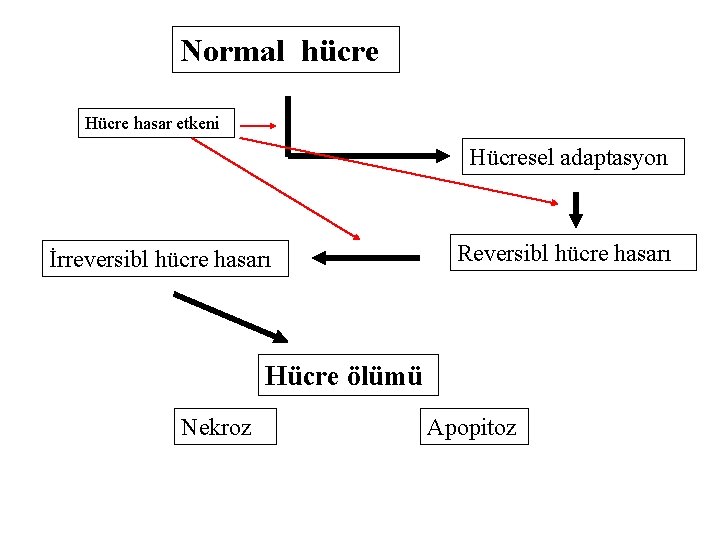

Normal hücre Hücre hasar etkeni Hücresel adaptasyon İrreversibl hücre hasarı Reversibl hücre hasarı Hücre ölümü Nekroz Apopitoz